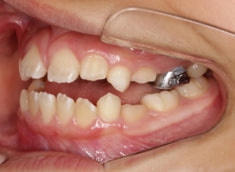

治療開始時

治療開始から11ヶ月